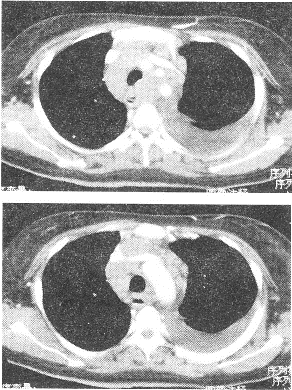

患者男性,咳嗽、咳痰6个月余,胸痛、乏力1个月。查体:左下肺呼吸音无。X线平片示:上纵隔影增宽,左侧中量胸腔积液。胸部CT如图所示:

正确答案:1.ADE;2.D;3.BC 解题思路:该例胸部CT可见纵隔淋巴结弥漫性淋巴结肿大.分布于血管周围,最可能的是淋巴瘤。未治疗的淋巴瘤较少出现坏死液化,增强扫描多为较均匀强化,这与淋巴结结核常为环形强化不同。